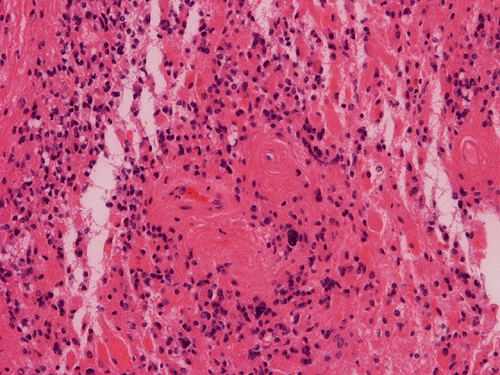

Pathology of the Case: MRI shows a large mass with the more solid component located in the lateral ventricles and the cystic component protruding into the cortical area. The solid area is enhanced (Panel A). On low magnification, the lesion has alternating area of high and low cellularity (Panel B) with scattered calcifications in some of the sections. Medium and high magnification demonstrates perivascular coronary arrangement of cytoplasmic processes (Panel C, D, and E). The nuclei are bland and mitotic figures are not readily seen. Randomly scattered brown pigment containing cells are found in multiple areas of the tumor (Panel F, G, and H). Scant lipidized cells with enlarged nuclei (Panel I) are also present. The tumor cells are strongly positive for glial fibrillary acidic protein (GFAP) (Panel J and K) and S100 protein but are negative for epithelial membrane antigen (EMA), neurofilament proteins, and NeuN. The overall Ki67 labeling is low but focal small areas (about the size of one high power field) has increased labeling. The pigment appears to be melanin on microscopic examination. These pigments are positive with Fontana-Masson stain (Panel L) but negative for Prussian blue stain for iron (Panel M). These features confirmed that these are melanin pigments. The pigment granules are positive for periodic acid-Schiff reaction (N), negative for Ziehl-Neelsen (acid fast) stain..

Melanocytic Cells

Although rare in the tumors of the CNS and peripheral nervous system, pigmented/melanonic differentiation have been described in meningioma, neurofibroma, schwannoma, paraganglioma, medulloblastoma, ganglioma of pineal gland, choroid plexus papilloma, pilocytic astrocytoma, pleomorphic xanthoastrocytoma, and ependymomas. These tumors should not be confused with the more common meningeal melanocytic tumor or metastastatic malignant melanomas. Pigmented cells in a primary neuroepithelial tumor comes from two source. The first is due to the formation of neuromelanin. In the normal brain, some neurons consistently form melanin and the pigmented neurons in the substantia nigra are the classic examples. Neuromelanin are positive with Fontana-Masson stain and they could be bleached. They can be positive for periodic acid-Schiff (PAS) reaction and Ziehl Neelsen stain (acid fast stain). However, they are negative for immunohistochemical markers for melanosomes such as HMB45. At the ultrastructural level, no genuine melasomes are found.